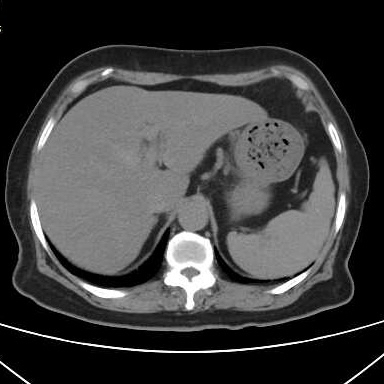

最近有几个吃山楂后形成胃结石的病历,第一个,老年女性,突发腹痛2天,持续性钝痛,阵发性加重,伴恶心,呕吐胃内容物,性状无异常,呕吐后无缓解,入院后抑酸治疗效果不理想,CT如下图。

考虑胃内结石,予以碳酸氢钠和可乐口服,第二天症状缓解,因为有别的问题,没有胃镜证实。

因为非影像专业,自己总结肠道植物性结石的特点,混杂密度,多数边缘规则,与正常胃、肠壁结构分界清晰,临床考虑多数急性起病,关键是要问近期是否有大量食用柿子、山楂、黑枣等富含鞣酸食物。